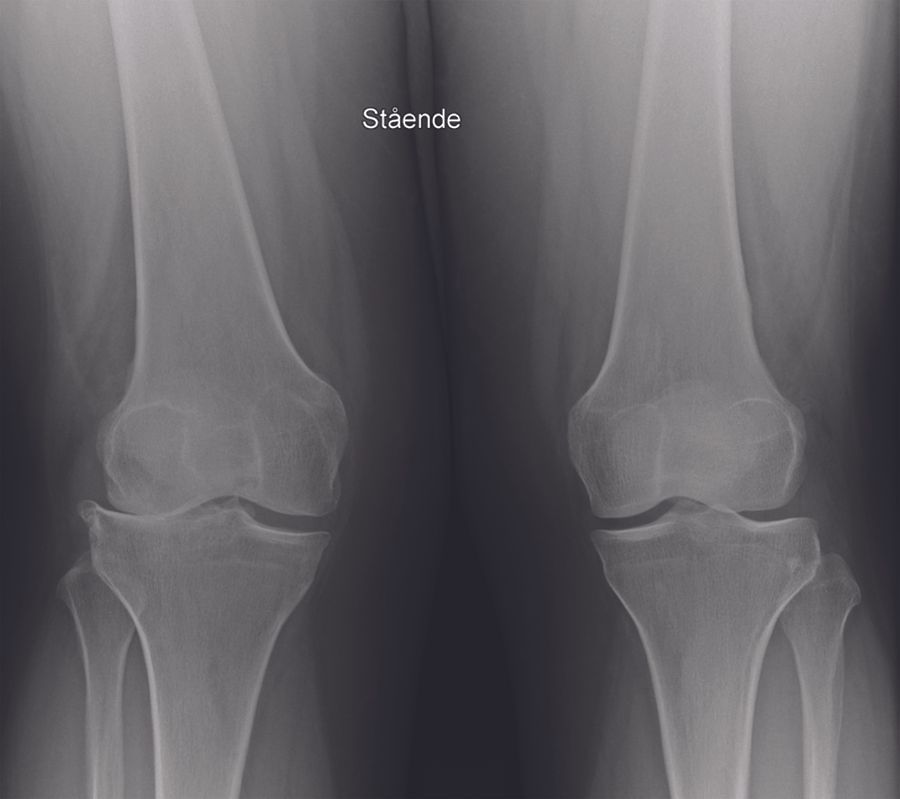

Technique Comment je réalise une prothèse unicompartimentale latérale du genou à plateau fixe , Anders Troelsen Hôpital Universitaire de Hvidovre, Copenhague, Danemark N°270 - Janvier 2018 ● 12 min de lecture